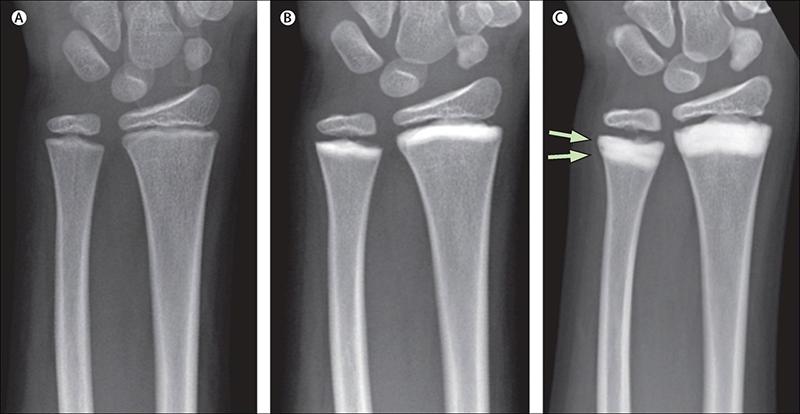

Остеосклероз — это заболевание, при котором происходит увеличение плотности костной ткани, что может привести к различным проблемам с опорно-двигательным аппаратом. Многие люди, столкнувшиеся с этой проблемой, отмечают, что симптомы могут быть неочевидными на начальных стадиях. Часто пациенты жалуются на боли в костях, особенно при физической нагрузке. Важно отметить, что диагностика остеосклероза требует комплексного подхода, включая рентгенографию и другие методы визуализации.

Диагностика

Первичный осмотр осуществляется врачом, который оценивает состояние костей на наличие болевых ощущений в различных положениях: как при движении, так и в состоянии полного покоя. Однако только на основании внешних признаков или пальпации сложно установить точный диагноз. Поэтому необходимо провести комплексное обследование. Диагностика включает в себя:

- УЗДГ МАГ;

- компьютерную томографию;

- магнитно-резонансную томографию.

От точности полученных данных зависит правильность диагноза и эффективность лечения. В некоторых случаях во время обследования обнаруживается, что остеосклероз подвздошной кости связан с другими заболеваниями, и для устранения недомогания необходимо сначала вылечить основную причину расстройства.